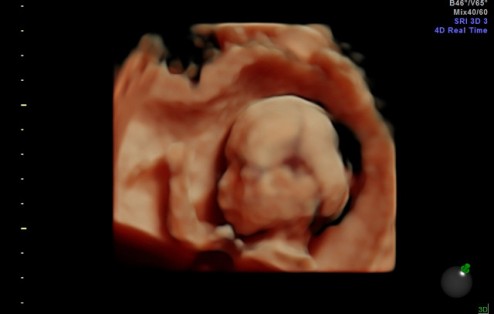

Sneak preview of MuiMui

MuiMui is a Chinese affectionate term for "little sister". It’s what we’re calling the baby for now. (And no, Mom, we’re not just keeping secrets, we haven’t decided on any name yet) This is 19 weeks, so a little less than 1/2 way.